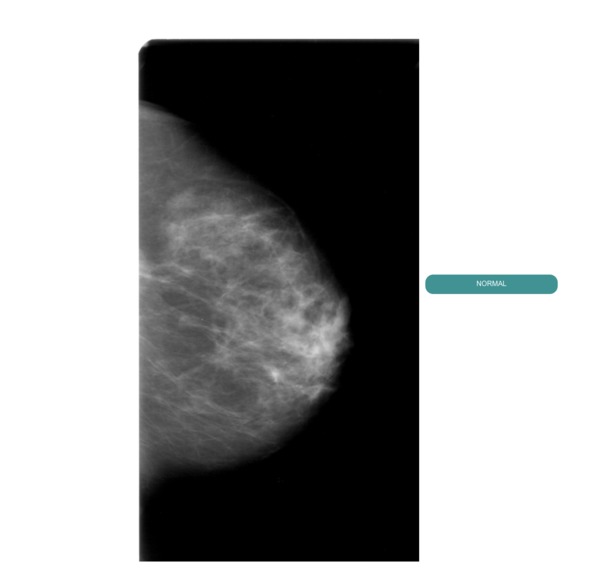

MediScan is web application powered by Deep Learning Models for predicting cancerous regions in breast mammograms. A user, for example a radiologist, would first select images to upload, a threshold value and then press submit. On submission, our backend will pass on the images to our deep learning models and will generate new images with bounding boxes if any are found. The bounding boxes will be clearly visible on the output images alongside with their probabilities.

We created a pipe for analysis of breast mammograms. We utilized 2 models. First an image goes through a Densenet model which predicts whether it is malignant or not. If malignant, the image is then passed into a FasterRCNN model which predicts cancerous regions with their corresponding probabilities. These models were both trained on DDSM dataset and were part of our research projects. We utilized PyTorch for training and inference of the models. We utilized Flask as the web framework for the web application.